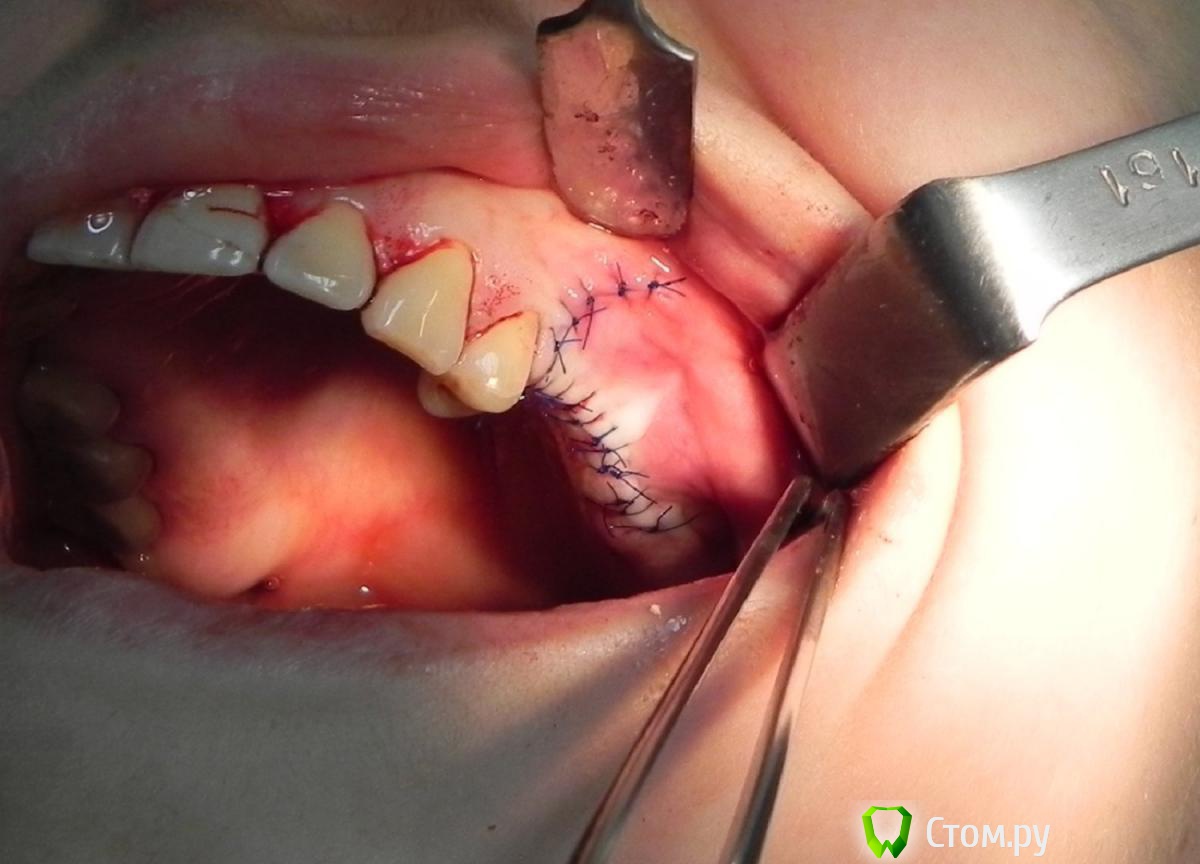

Kostoprav Опубликовано 30 мая, 2015 Автор Поделиться Опубликовано 30 мая, 2015 все работает, чистая синтетика без ауто! это не единичный случай. 2 Ссылка на комментарий

Kostoprav Опубликовано 12 июня, 2014 Автор Поделиться Опубликовано 12 июня, 2014 одновременно поставить -высоты кости не хватило ? 1-2 мм , я рисковать не захотел. 2 Ссылка на комментарий